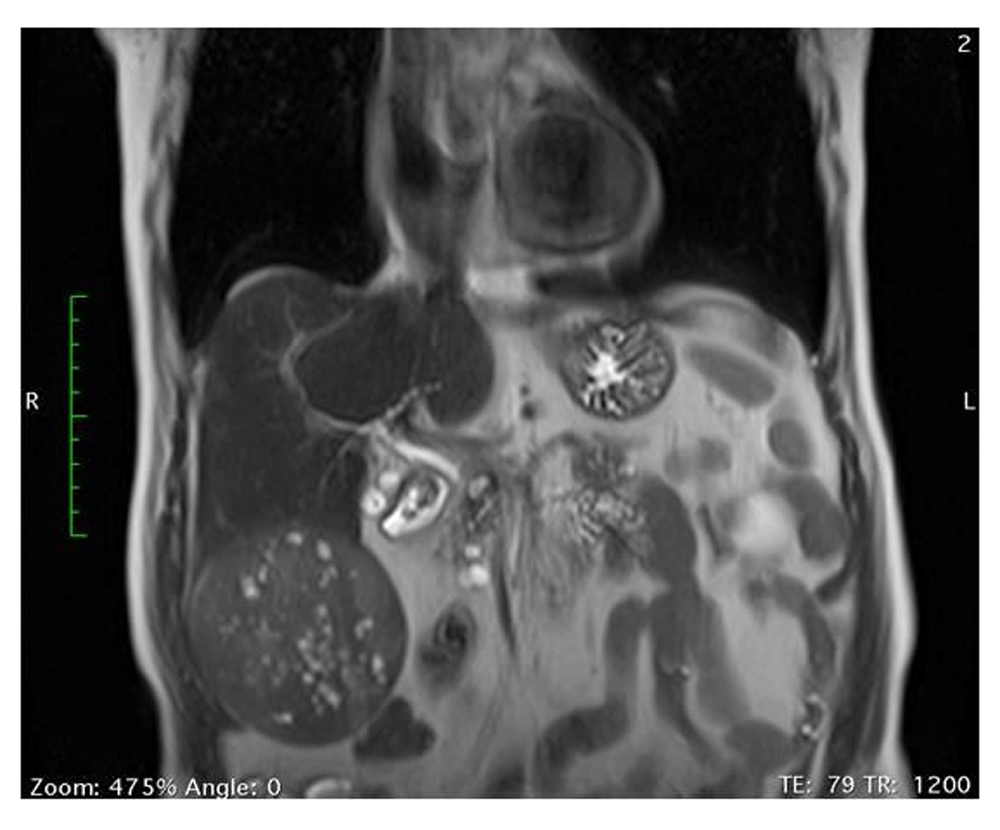

An 81-year-old male patient with deteriorating right subcostal pain and high values of serum gamma-glutamyl transpeptidase and alkaline phosphatase underwent an abdominal ultrasound scan, which revealed the presence of a heterogeneous tumor 10cm in diameter, located in the right hepatic lobe, along with mild steatosis of the liver. The patient underwent an abdominal and thoracic computed tomography and an abdominal magnetic resonance imaging. They showed a heterogeneous tumor in the hepatic segment VI, which presented intense arterial uptake of the intravenous contrast followed by quick venous washout, without any sites suspicious for metastases (Figure 1). Additionally, he underwent an ultrasound-guided biopsy of the mass, which revealed the presence of a moderately differentiated hepatocellular carcinoma (HCC). Serum levels of alpha-fetoprotein (AFP) were within normal range. The patient’s medical history included arterial hypertension, type 2 diabetes mellitus, atrial fibrillation and chronic obstructive pulmonary disease, rendering him a patient with an ASA (American Society of Anesthesiologists) score 3, but no viral hepatitis, cirrhosis or any other liver pathology, apart from mild liver steatosis. The patient’s body mass index (BMI) was 26.

c36d9fa9-8c26-4fc6-a354-f869c572ff31_figure1.gif

Figure 1. Magnetic resonance imaging of the giant liver lesion.